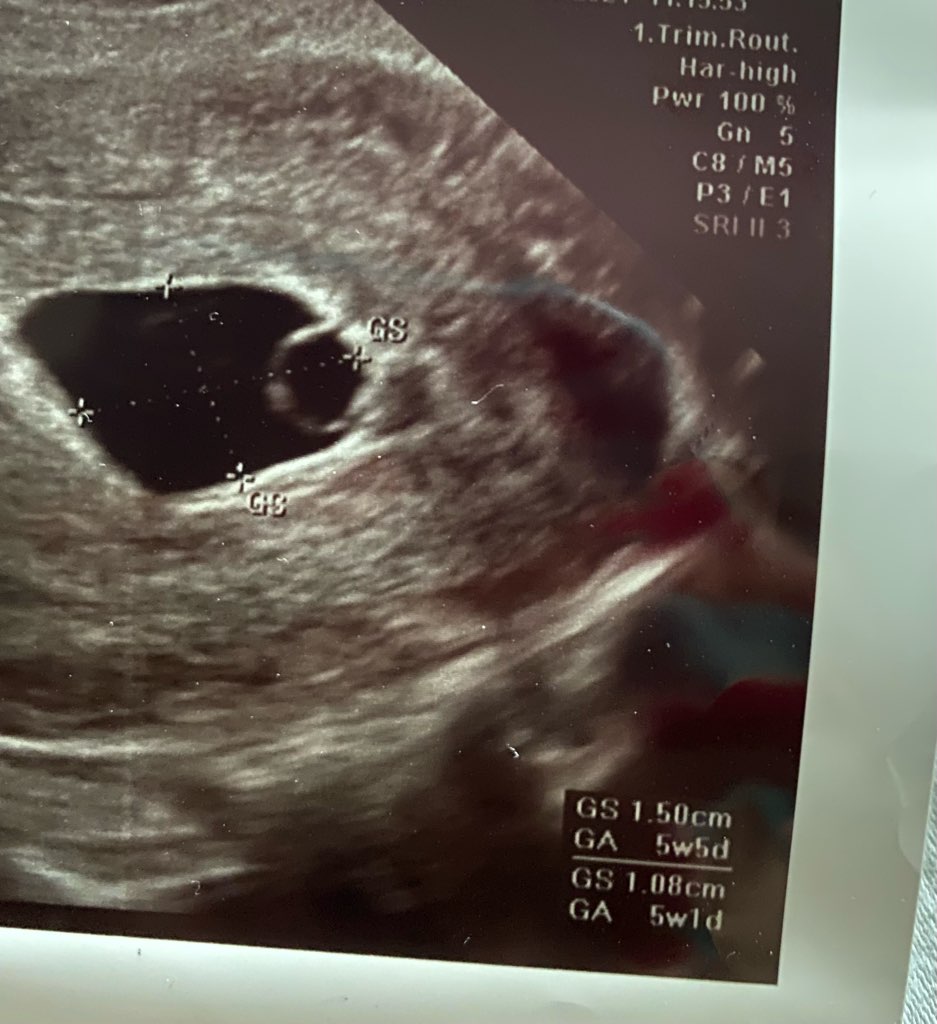

nie poddajemy się! Udało nam się umówić jeszcze dziś wizytę o 17 :) jak na spokojnie spojrzałam na ten drugi obraz usg od lekarza, który stwierdził, że nic nie ma to widać tam maluteńki zarodek przyklejony do pęcherzyka żółtkowego.

Podrzucam Wam tu zdjęcie